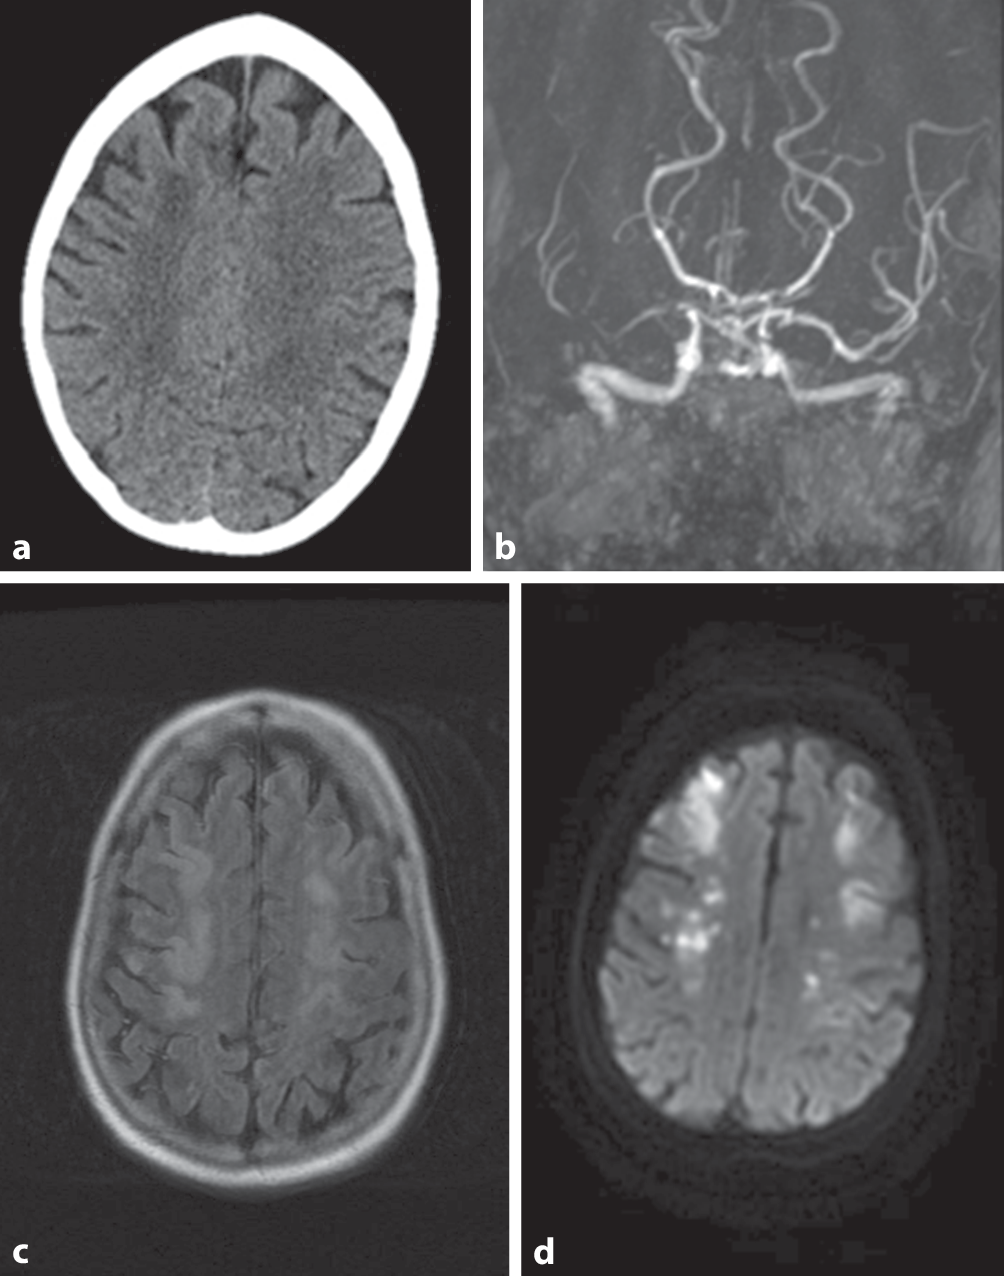

Bei einer 56-jährigen Patientin wurden bei einer Femurfraktur eine komplikationslose offene Reposition und Osteosynthese mittels eines Gammanagels durchgeführt. Fünf Tage später entwickelte sie eine Hemisymptomatik links und eine Sepsis unklarer Genese mit einem CRP von 382 mg/l (Normwert: < 5 mg/l), Panzytopenie und Katecholaminpflichtigkeit. Im cMRT zeigten sich bihemisphärisch akute Ischämien. Es erfolgte die Übernahme auf unserer Neurointensivstation mit Umkehrisolierung. Anamnestisch war ein V. a. Neurosarkoidose unter Langzeitkortison- sowie MTX-Therapie bekannt. Die ausführliche Infektfokussuche, inklusive Liquordiagnostik und der computertomographischen Darstellung des implantierten Gammanagels, ergab nur einen Candidanachweis im Urin, was als Kontamination gewertet wurde. Trotz bereits 5‑tägiger Behandlung mittels Meropenem und Vancomycin fieberte die Patientin erneut auf mit einem CRP-Anstieg und einer deutlichen klinischen Verschlechterung des Zustandes – soporöse komatöse tetraplegische Patientin mit positiven Pyramidenbahnzeichen bds., oraler Kandidose, progredienten petechialen Einblutungen, gespanntem Abdomen, träger Peristaltik, Druckdolenz im Unterbauch und pathologischem Atemmuster. Die bildmorphologische Verlaufskontrolle zeigte progrediente bihemisphärische Infarkte (Abb. 1). Duplexsonographisch fielen ubiquitäre Flussbeschleunigungen in den intrakranialen Gefäßen auf (MCA bds., im Verlauf auch PCA bds.), CT-angiographisch wurden eine hochgradige ACI-Abgangsstenose rechts und sowie in der Pars cavernosa/Karotissiphon und eine M1-Stenose rechts und eine leichtgradige ACC-Stenose links beschrieben, im Verlauf auch kaliberschmächtige ACA bds.

Transversale Schicht im cCT, MRA initial (a,b), transversale T2-FLAIR-Wichtung und Diffusionswichtung im Verlauf (c,d)